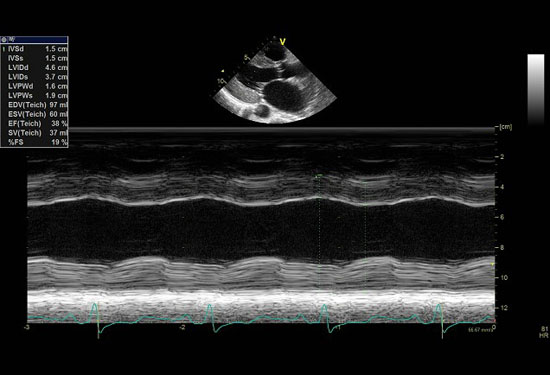

Hypokinesis of the left ventricle and moderately enlarged left atrium. It also showed a normal sized ventricle with multiple trabeculation in the mid LV cavity and apex ... Document Viewer

Normal hypokinesis hypokinesis dyskinesis Gated SPECT Normal 233 0 0 0 Mild hypokinesis 13 27 0 0 Severe Myocardial perfusion defects were observed in all except 1 patient. Perfusion defect size involved 16% ± 15% of ... Retrieve Full Source

Abnormal, Autoquant Adenosine Myocardial Perfusion Heart Imaging ID: GOLD307725 Date: 1996-03-19 Age: 46 Sex: M John Doe Phone (310) 423-5000 hypokinesis in the septal and apical walls. Conclusion: Perfusion Prob abnormal (Reversible and ... Doc Viewer

76 YOM has a history of myocardial infarction 13 years ago. Coronary angiogram showed occlusion of the right coronary artery. angioplasty attempt was unsuccessful.Echocardiography showed inferior,posterior and lateral wall hypokinesis. ... View Video

MYOCARDIAL PERFUSION IMAGING FINAL REPORT

MYOCARDIAL PERFUSION IMAGING Stress/Rest (or Rest/Stress) consistent with myocardial ischemia. Myocardial perfusion imaging was performed at rest SPECT imaging demonstrates hypokinesis/dyskin-esis/akinesis of the ____ (location). ... Doc Retrieval